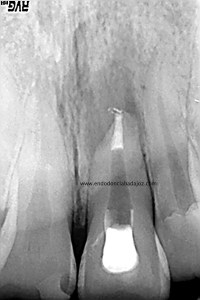

La paciente fue llamada a revisión al año:

Y más tarde, a los dos años:

Esta paciente nos llegaba sin sintomatología, y la lesión ha regenerado correctamente, con lo que podemos decir que hemos tenido éxito en el tratamiento.